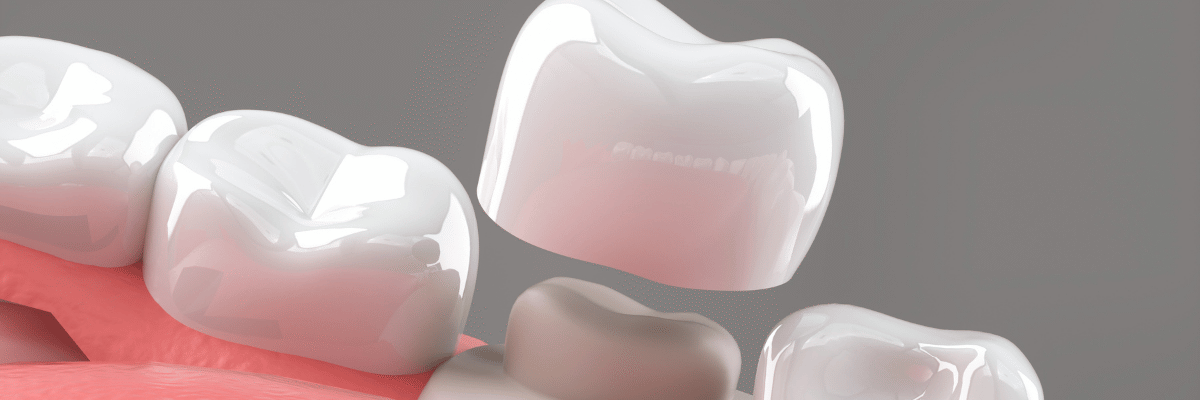

A dental implant is surgically inserted into the jawbone, where it gradually integrates with the bone for stability. Once healing is complete, a custom crown or bridge is placed to restore function and aesthetics. Crowns can also strengthen weakened teeth, while bridges help fill gaps caused by multiple missing teeth.